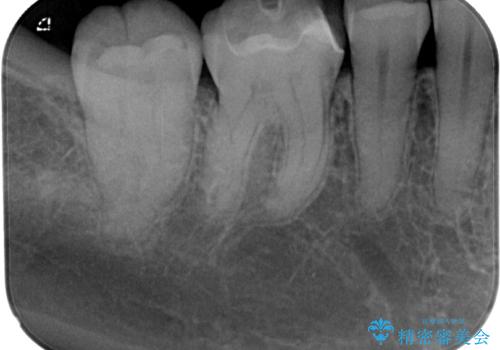

歯と歯茎の間に圧排糸と言われる糸を入れてシリコーン印象材にて精密な型どりをしました。

ハイブリッドインレーの装着時には、唾液の侵入を防ぐために、ラバーダム防湿を行いました。

歯と歯の間の虫歯をコンポジットレジンや保険のメタルインレーで治すと段差ができたりして清掃性が悪くなるので、セラミックインレー修復やゴールドインレー修復などの適合の良い詰め物で治療することをオススメします。